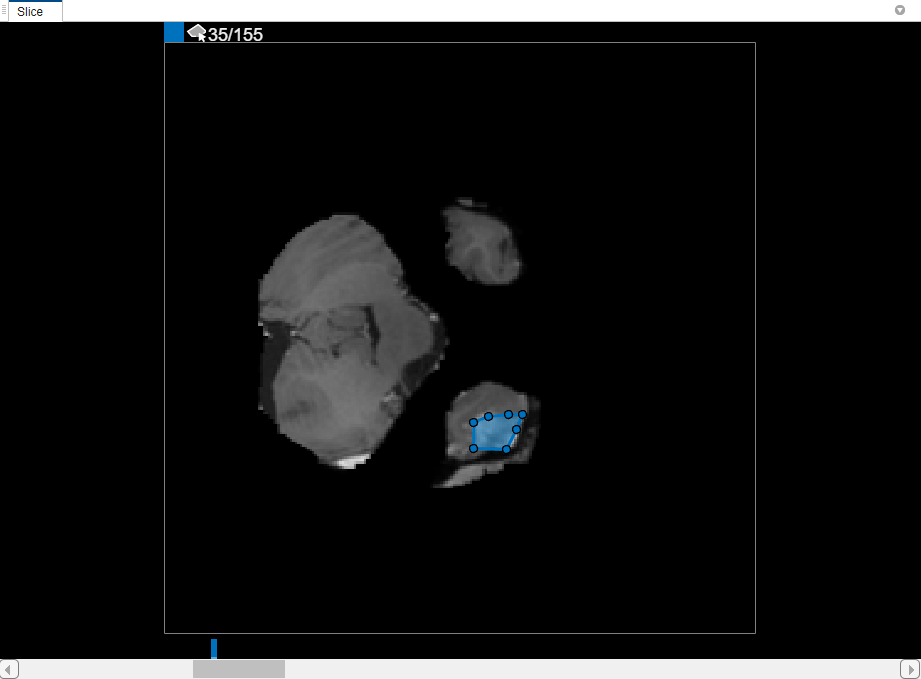

In the Slice pane, navigate to the slice where the object first appears, slice 35, and draw an outline around the object. For this example, use the Polygon drawing tool. Click to create a vertex, then move the cursor and click again to create a second vertex with a straight line connecting them. Continue this process to create a connected line. To add additional vertices after you finish drawing, double-click on the ROI edge.

To use interpolation, you must first manually define the region on two slices. You have already defined the region on the first slice where the object appears, slice 35. Use the same process to define the region on the last slice where it appears, slice 88. The app places two bars on top of the slider, using the color associated with the label, to indicate the slices with ROIs.